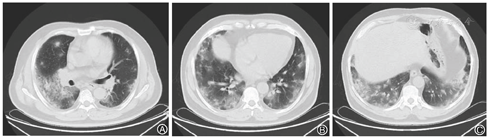

患者,男,56岁,因发热、咳嗽、咳痰伴活动后胸闷3 d于2019年9月10日入院。患者3 d前无诱因出现发热,体温在38 ℃左右,无畏寒、寒战,无盗汗,发热无明显规律性,伴咳嗽,咳少许黄白痰,无胸痛、咯血,伴胸闷、憋气,活动后加重,无消瘦,无头晕、恶心、呕吐,门诊行胸部CT考虑双肺感染性病变,为进一步诊治收住院。患者入院的20 d前在日本出差时出现咽痛,自服感冒药物(具体不详)后好转。既往有“冠心病、高血压”病史4年,2015年行冠脉造影示冠状动脉肌桥,无吸烟史,无禽类、粉尘、工业毒物接触史。体格检查:体温36.5 ℃,脉搏84次/min,呼吸23次/min,血压137/75 mmHg(1 mmHg=0.133 kPa),神志清,全身皮肤无皮疹,口唇发绀,双肺呼吸音粗,双下肺可闻及湿性啰音,心率84次/min,律齐,未闻及杂音。腹软,无压痛、反跳痛,双下肢无浮肿,四肢肌力正常。入院后查动脉血气分析(未吸氧):pH为7.374,二氧化碳分压为39.4 mmHg,氧分压为52.6 mmHg,血氧饱和度为84.8%,乳酸为1.1 mmol/L;血常规:白细胞计数为7.68×109/L,中性粒细胞百分比为 72.1%,淋巴细胞百分比为17.2%,红细胞计数为4.47×1012/L,血沉为16 mm/h;血生化:白蛋白为36.3 g/L,葡萄糖为6.44 mmol/L,乳酸脱氢酶为284 U/L,C反应蛋白为30.9 mg/L,三酰甘油为2.25 mmol/L;血凝常规:纤维蛋白原含量为4.67 g/L;肺肿瘤标志物CYFRA21-1为11.3 ng/ml;降钙素原为0.052 μg/L;病原学检查:半乳甘露聚糖试验(GM试验)为0.38 μg/L;痰细菌培养、真菌涂片、结核菌涂片阴性;肺炎支原体抗体、衣原体抗体、呼吸道合胞病毒抗体、出血热病毒抗体、真菌葡聚糖、巨细胞病毒核酸检测均阴性;免疫相关:抗核抗体(ANA)、抗环瓜氨酸肽抗体(CCP)、抗中性粒细胞胞浆抗体(ANCA)均阴性;机体细胞免疫评价正常;尿常规、大便常规、肌钙蛋白、脑钠肽均正常;乙肝表明抗原、丙肝抗体、梅毒抗体、HIV抗体均阴性;心电图示窦性心律、心电轴中度左偏、ST-T异常;胸部CT考虑双肺感染,建议治疗后复查,心影饱满,冠脉钙化,两侧胸膜略增厚(图1A~C)。入院后给予经鼻高流量湿化氧疗(氧浓度50.0%,氧流量50 L/min),美洛西林舒巴坦(2.5 g,1次/12 h)联合左氧氟沙星(0.6 g,1次/d)抗感染,奥司他韦胶囊(75.0 mg,2次/d)抗病毒,多索茶碱(0.3 g,1次/d)扩张支气管,溴己新(4.0 mg,2次/d)止咳化痰,低分子肝素钠(5 000 U,ih,1次/d)抗凝,硝苯地平缓释片(10.0 mg,2次/d)降压治疗,患者体温逐渐降为正常,但活动时胸闷无改善,经皮血氧饱和度在95.0% 左右(上述氧疗情况下),考虑抗感染解痉平喘治疗效果不佳,不除外间质性肺病,遂于9月14日加用甲泼尼龙(40.0 mg,1次/12 h)静滴,自觉症状略有好转,于9月17日复查胸部CT示双肺片状影较前增多(图2A~C),提示疾病进展,与患者及家属沟通后于9月17日行床旁支气管镜检查,镜下见左右肺各叶段支气管通畅,黏膜轻度充血,可见少量白色泡沫样分泌物,未见狭窄、出血及新生物(图3),于右肺下叶后基底段行肺泡灌洗及透壁肺活检,肺泡灌洗液(BALF)细胞分类示淋巴细胞百分比为63.0%,中性粒细胞百分比为24.0%,巨噬细胞百分比为8.0%,上皮细胞百分比为5.0%;BALF细菌、真菌涂片和培养均阴性;BALF结核菌涂片、结核菌核酸扩增检测(Gene Xpert)均阴性;BALF脱落细胞学检查阴性;BALF-GM试验0.55 ng/ml;BALF病原微生物宏基因组检测(NGS)示产黑色素普雷沃菌(序列数12)、龋齿罗氏菌(序列数7)、简明弯曲杆菌(序列数1);支气管镜肺活检病理考虑肺间质纤维化(图4)。患者对治疗反应不佳,为排除肿瘤于9月20日行正电子发射计算机断层显像(PET-CT)示双肺多发斑片影、结节灶,大部分见支气管充气征,部分结节边缘见分叶和毛刺,SUVmax 6.4,考虑感染性疾病,霉菌感染可能性大,肉芽肿性炎和MALT淋巴瘤不除外(图5)。请北京协和医院专家会诊,考虑ILD,不除外结缔组织病相关,建议加大甲泼尼龙(80.0 mg,1次/8 h)用量,升级抗生素为美罗培南(1.0 g,1次/8 h),完善肌炎谱13项示抗Jo-1抗体阳性,最终诊断为抗Jo-1抗体综合征,加用环磷酰胺(0.4 g,1次/周)静滴8次,并逐渐减少甲泼尼龙用量,患者胸闷症状明显好转,2019年11月18日复查胸部CT示肺内病变较前明显吸收好转(图6A~C),随访1年,病情稳定。